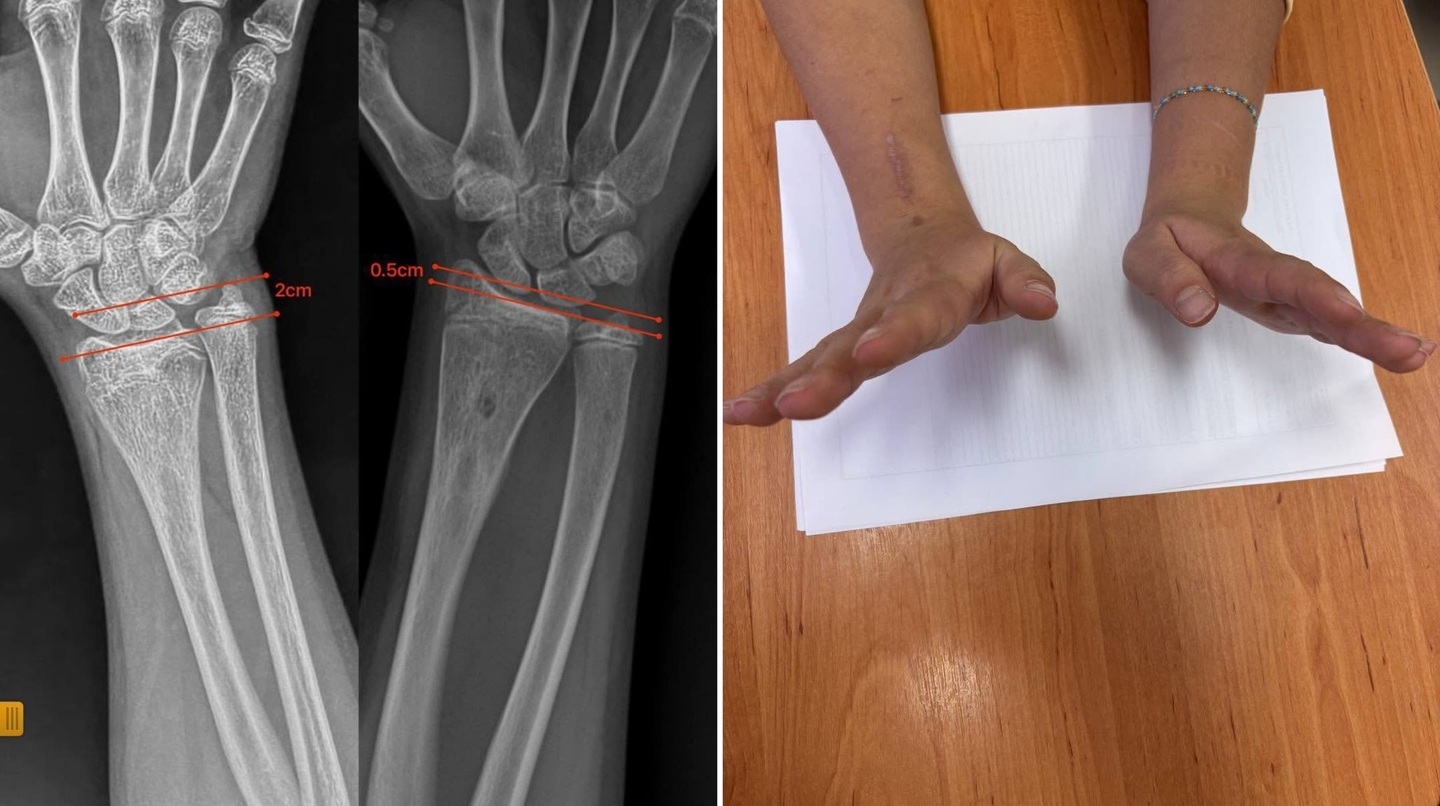

Обстеження показало, що ріст однієї з кісток був порушений через утворення кісткового містка, який блокував природний розвиток і спричиняв деформацію.

Під час операції лікарі видалили кістковий місток під контролем ендоскопа. Завдяки такому щадному методу вдалося обійтися без остеотомій та встановлення металоконструкцій — природний ріст кістки відновився самостійно.

Через сім місяців форма передпліччя повністю нормалізувалася, ріст кістки відбувається правильно, а функція кінцівки збережена у повному обсязі.

Фото: Закарпатська обласна дитяча лікарня.